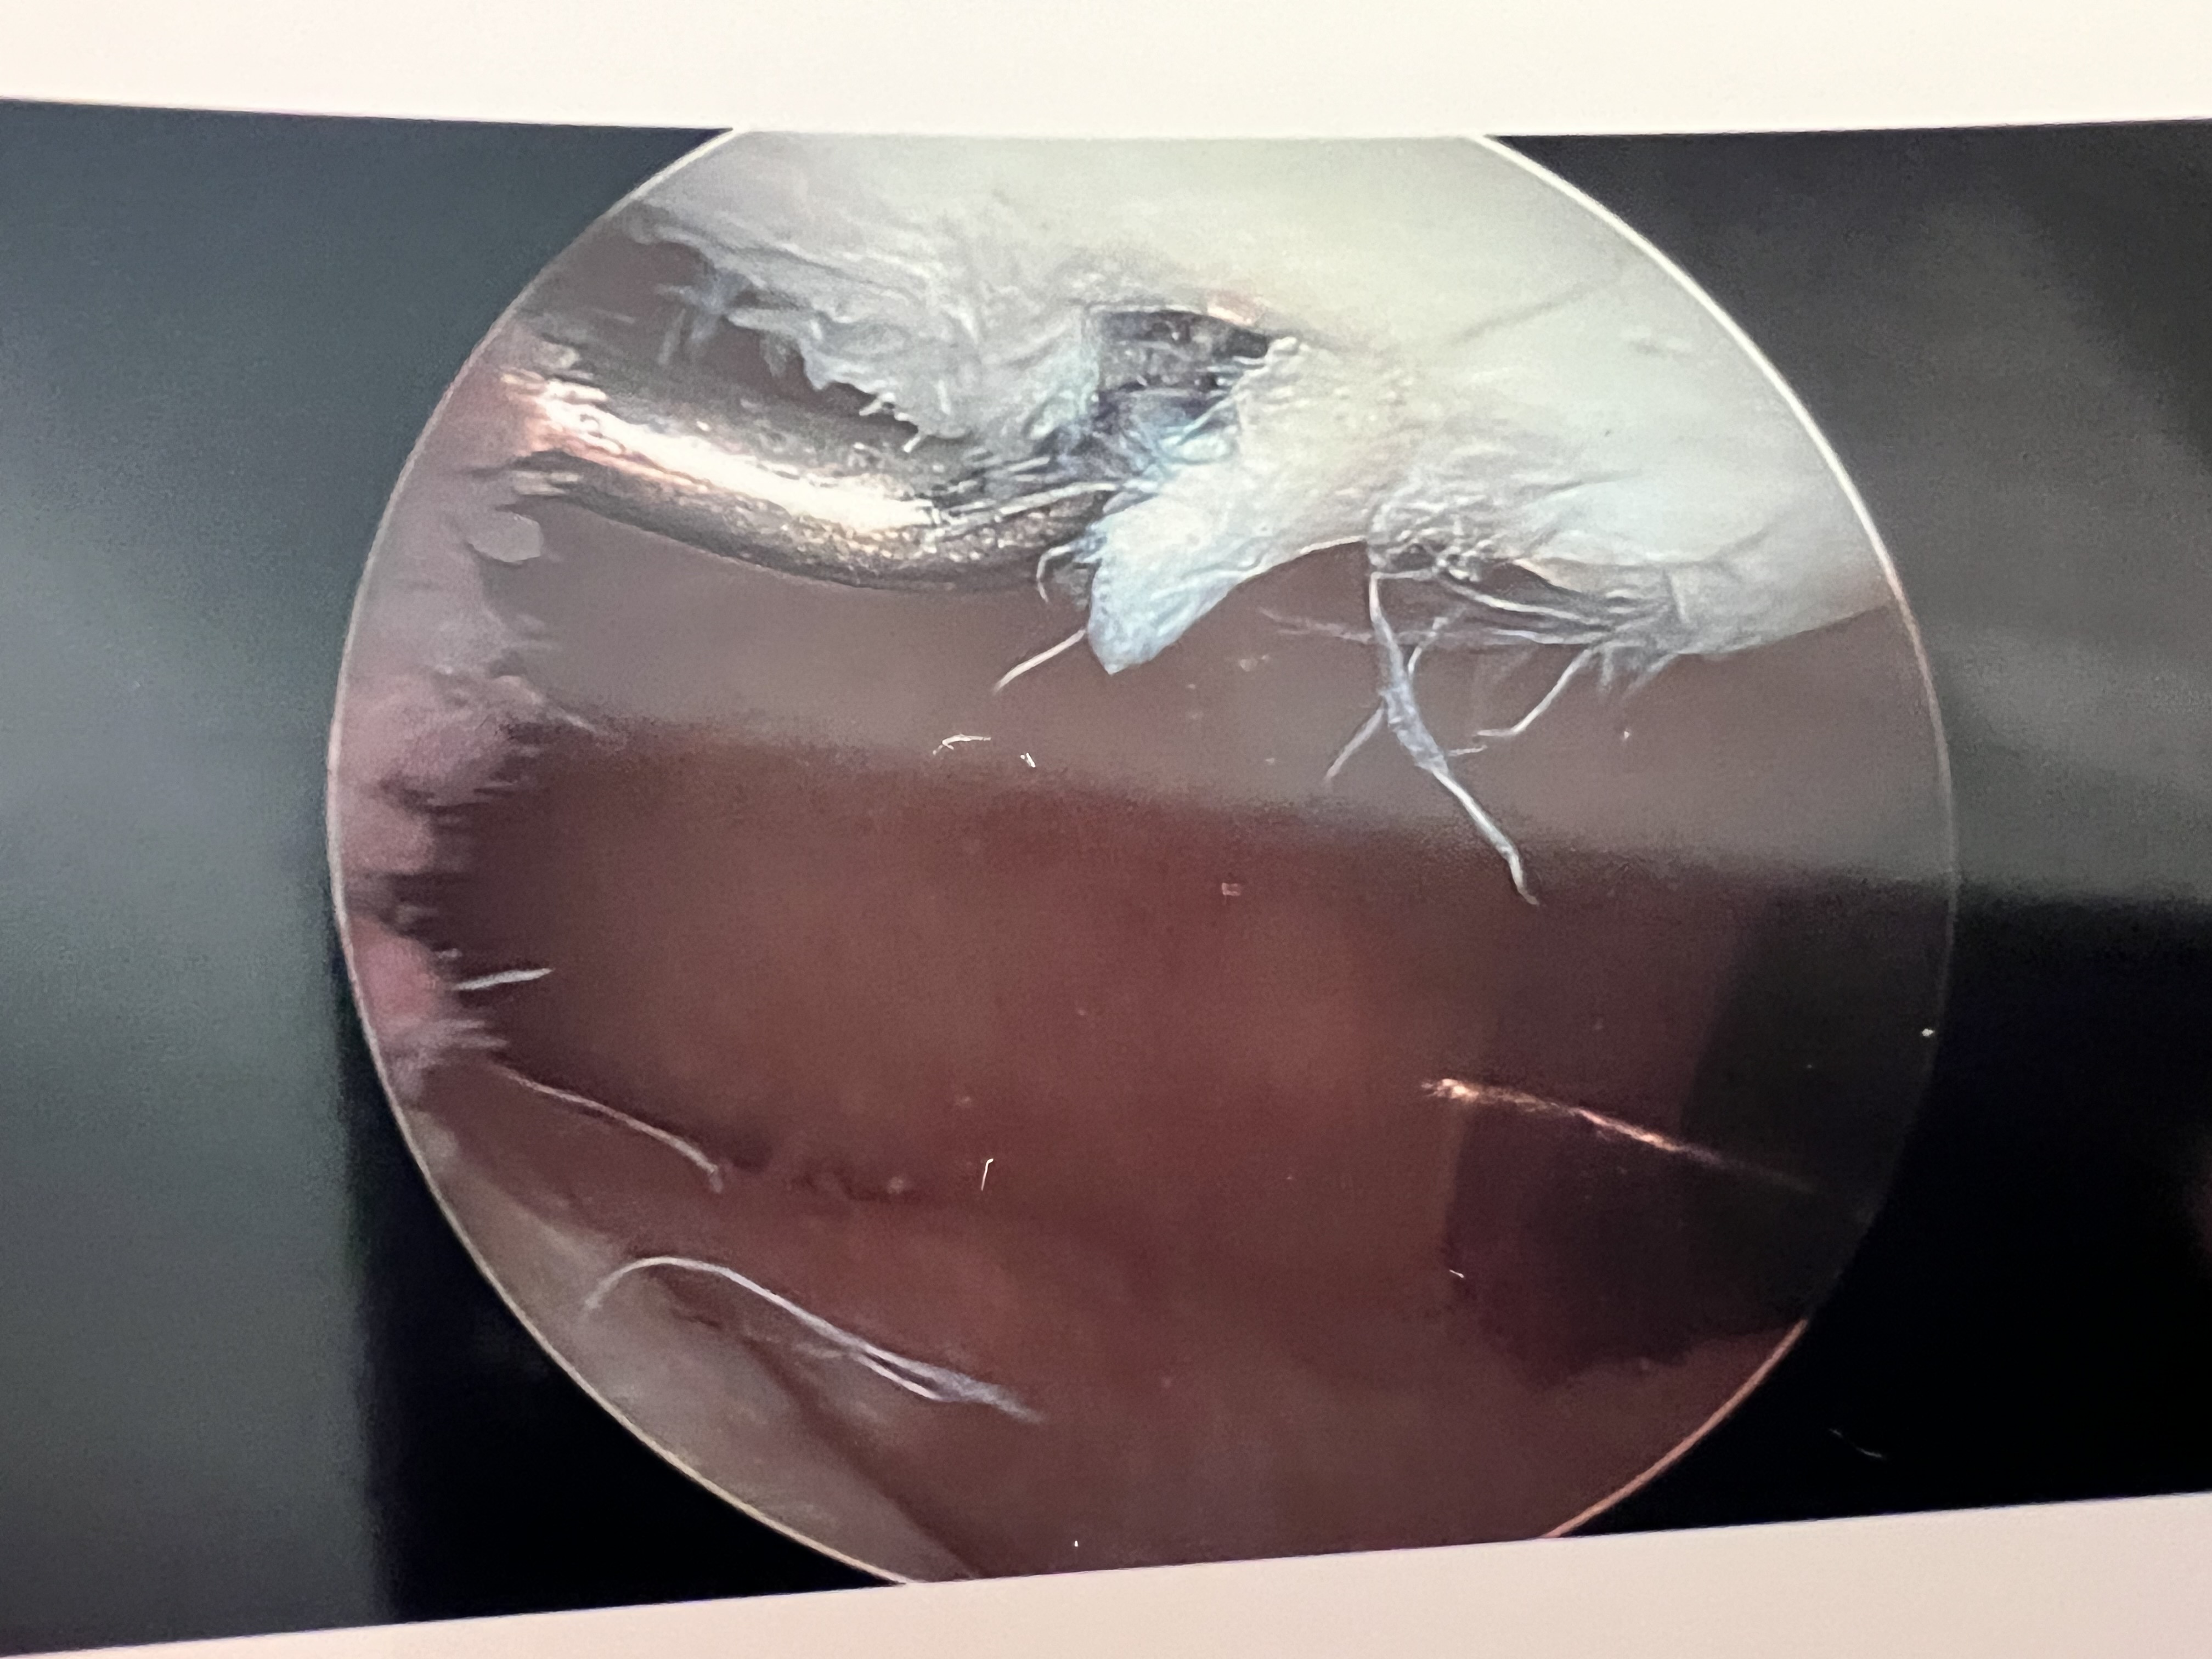

Thursday, April 4, 2024

Knee surgery on right knee, Meniscus repair.

Knee Surgery: Left knee meniscus repair.

Listen, I’m not a doctor, and I have not had my post-op review with the Ortho team yet, but I’m gonna guess this little guy above was an issue.